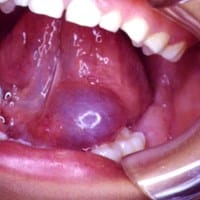

Cirugía por absceso en la lengua.

Quisiera saber si alguno de ustedes sabe aproximadamente el costo de una cirugía de un absceso debajo de la lengua, en México. Es algo así, sólo que un poco más pequeño: .